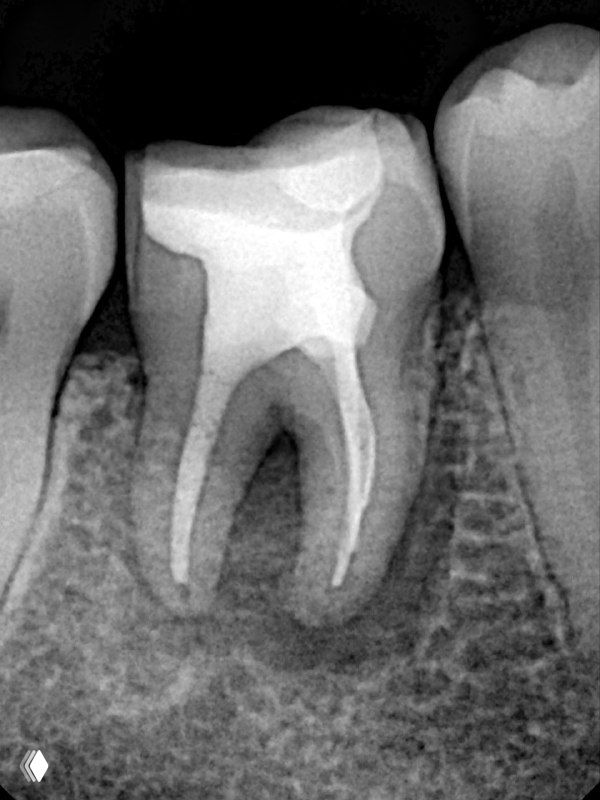

- 6)Оставляю кальций на неделю для профилактики заместительной резорбции. Она все равно будет на реколлах, но в меньшем объеме.

- 7) Пломбирую вертикальной компакцией гуттаперчи, в то же посещение делаю билдап. А вот коронкой зуб покрывает уже через 6 мес после реколла.